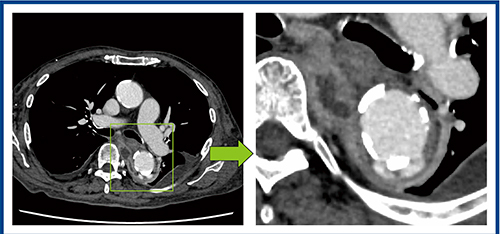

壁性状の評価が有効であった一例を示す。症例2は80歳代,男性,感染性大動脈瘤である。病変部を見ると,3〜6時方向は壁が明瞭に描出されているが,6〜10時方向は不明瞭である(図2)。この部分には,大動脈に接する膿瘍腔があり,炎症反応に伴って壁構造が崩れている様子を視認できているものと考えられる。

図2 症例2:感染性大動脈瘤における血管壁の描出